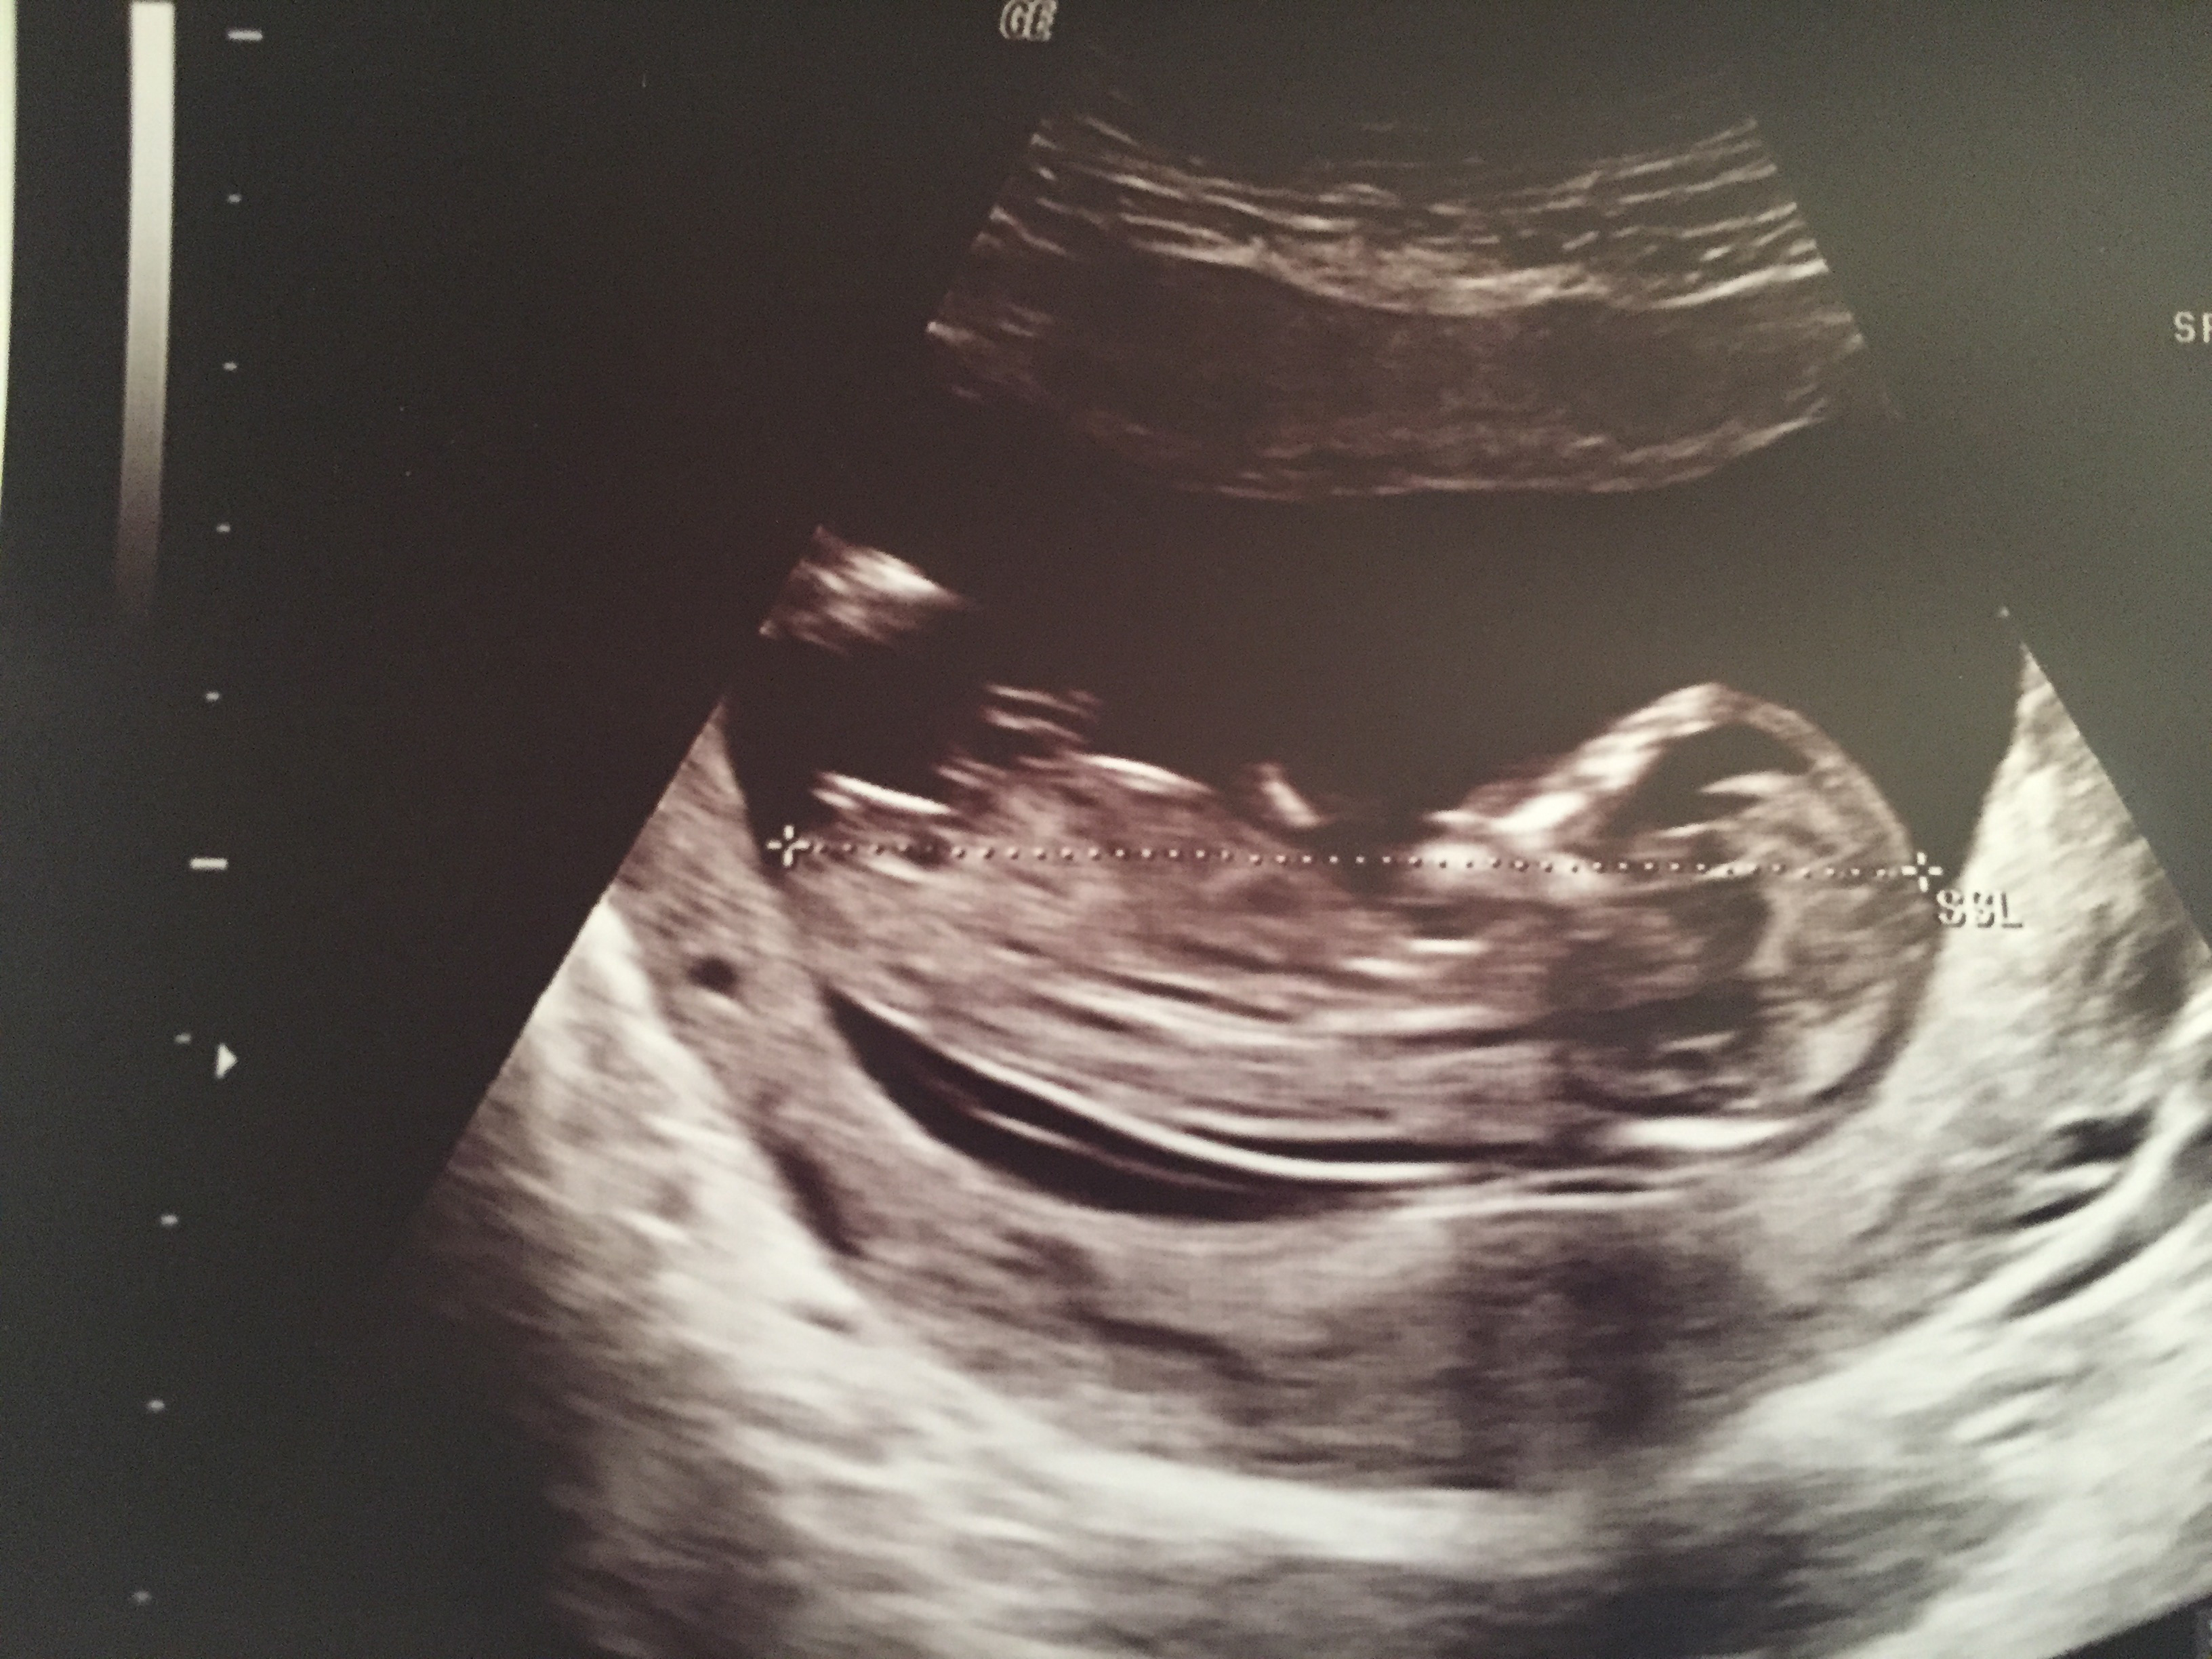

12w 5 days ultrasound pic! I am so excited :-) Is this the nub? If yes what do you think? Thank you for your guesses!Attachment 27112

It looks like a girl nub.